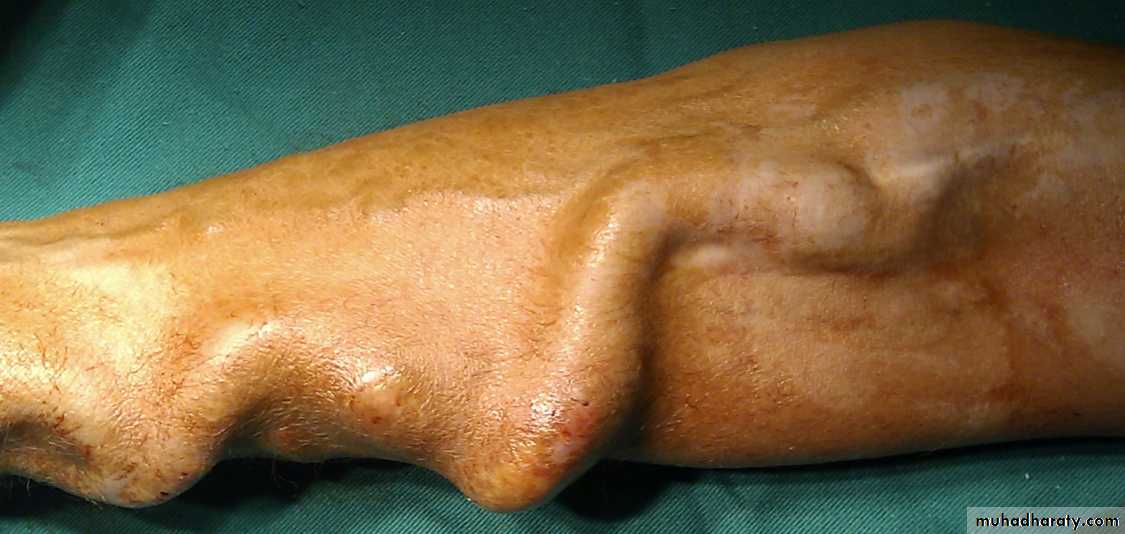

History; too shy to take of his shirt in the pool!